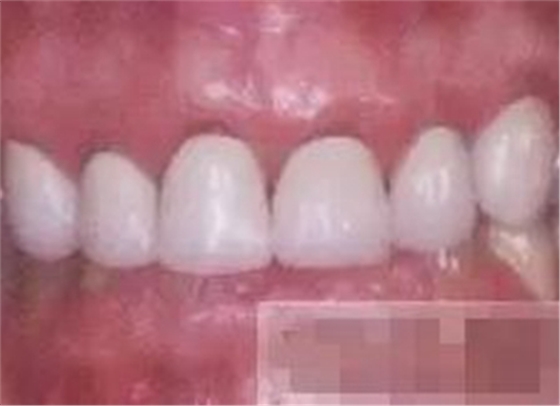

【充填完成】

1、樹(shù)脂貼面平齊牙齦邊緣是最佳設(shè)計(jì),或者使用齦上邊緣 。

2、釉質(zhì)邊緣要用橡皮輪拋光。拋光可以去除懸釉。這樣經(jīng)過(guò)車針打磨過(guò)的釉質(zhì)表面會(huì)更加均一,形成良好的邊緣封閉。

3、纖維樁通常深入到根管的1/2至2/3處。因?yàn)樽罴训恼辰有Чl(fā)生于根管的冠1/3和中1/3。由于根1/3的牙本質(zhì)小管往往不能充分敞開(kāi),此區(qū)域幾乎沒(méi)有粘接作用發(fā)生,所以,根管纖維樁放置的深度無(wú)需超過(guò)根中1/3。

4、修整纖維樁按所需長(zhǎng)度裁截纖維樁 在有水條件下 用切割砂片或車針截取纖維樁,切勿使用鉗子,剪刀或鑷子以免破壞樁的結(jié)構(gòu)。

5、為了提高樹(shù)脂的聚合轉(zhuǎn)化率,我們可以用防氧化劑,或者用甘油涂沫于樹(shù)脂的表面,或者修復(fù)體的間隙處,以利于樹(shù)脂的聚合。然后再進(jìn)行打磨拋光。